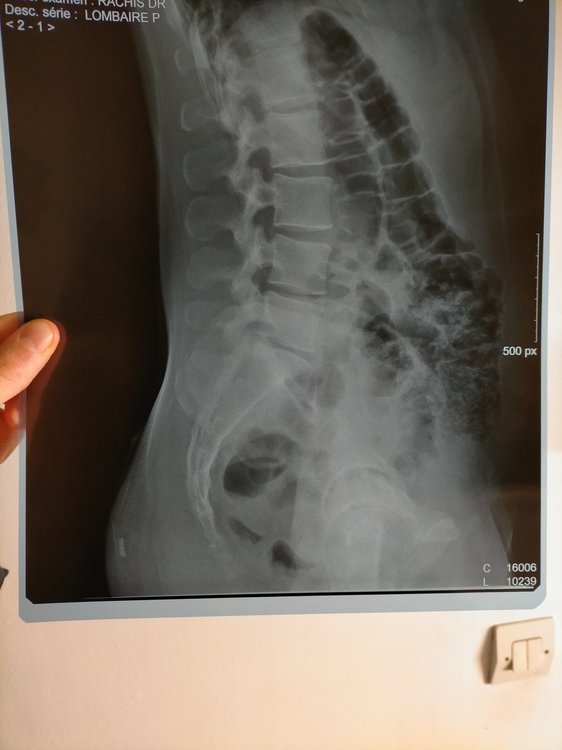

Bonjour à tous, Tout d'abord bravo pour ce forum et pour le travail de M. Blondeau. J'ai parcouru de nombreux sujets et appris beaucoup de choses. Je me permets un nouveau sujet, étant un peu perdu dans mes démarches et mon positionnement. Je pratique le vélo depuis 6 mois, de manière plutôt assidue, environ 1000km par mois (home trainer en semaine et sorties de 150km en moyenne le weekend).Depuis le confinement, 100% home trainer. Mon objectif 2021 est l'ultra distance type bikingman et de longs voyages à vélo pendant les vacances, en autonomie (vélo chargé). J'ai développé un syndrome rotulien aux deux genoux (dont droit +++) à la fin de l'été 2020, à cause d'une selle réglée trop bas, d'une mauvaise technique de pédalage et d'un trop grand nombre de kilomètres (j'ai largement grillé les étapes). Résultat : trois semaines d'arrêt, médecin du sport, IRM/Radio, infiltrations genou droit et étude posturale. J'ai repris progressivement depuis l'étude posturale mais j'ai développé de nouvelles douleurs : arrière des genoux (ça tire pendant effort et douleurs les jours qui suivent) + tendons d'achille (si je force trop ou roule trop de km/D+, j'ai des inflammations le lendemain et/ou douleurs). J'ai aussi la sensation d'avoir la jambe droite plus courte, de devoir forcer et d'avoir moins de puissance/contrôle quand je pédale rond. Mon ostéo a remarqué une différence de 2/3 mm entre ma jambe droite et gauche. Je pense que ma selle est trop haute . Le physio qui a réalisé mon étude postale m'a invité à baisser ma selle d'1 cm mais les douleurs sont encore là. Je ne veux pas baisser trop par peur de réveiller les problèmes initiaux (syndromes rotuliens). Je fais depuis ma reprise du gainage, des étirements, du yoga, du renforcement quotidien et je fais attention à ma récup et la progressivité de la charge de travail mais on est encore loin de la perfection physiquement et j'ai toujours des douleurs. MA QUESTION : en me filmant sur mon home trainer, j'ai remarqué une franche bascule du bassin vers la droite. J'aimerais ajouter une rehausse cale de 5mm pour compenser et rendre mon réglage de hauteur de selle moins compliqué. Certains disent que c'est une bonne idée (exemple), d'autres que non. Que me conseillez vous ? Voici une videos de dos sur home trainer avec selle à 73,8cm (pas de douleur derrière les genoux ni aux talons d'achille. Sensation de confort global mais tension dans les genoux/rotules). En dessous une video 10 jours plus tot, de profil, avec elle à 75cm (gene derrière les genoux et talons d'achille) Mesures étude posturale : Membre supérieur : Acromion - styloide cubitale : 55cm Tronc : Grand trochanter - Milieu Acromion : 57cm Femur : grand trochanter - condyle externe genou = 43cm à gauche et 43 cm à droite Jambe : condyle externe genou - Malléole externe cheville = 43cm à gauche et 43 cm à droite Entre-jambe : 85cm (mais je trouve entre 83 et 84 en mesurant moi même) Flexibilité : bof bof mais j'y travaille. Cotes étude posturale : Hauteur cadre et longueur du cadre : 54 (OK) Inclinaison : 155mm Axe de pédalier - Apex de selle : 76 cm (douleurs depuis) Fond de selle - axe de guidon : 79 cm (OK) Sortie de potence : 30 mm (OK) Longueur potence : 100 mm (OK) Longueur manivelle : 170mm (OK) Largeur guidon conseillée : 42cm (OK) Cales chaussure : Look keo rouge (OK) avec conseil de réglage suivant : "tout à fond vers le haut de la chaussure". J'ai ajouté une rehausse cale de 1mm à droite depuis que mon osteo a constaté le différence de hauteur de jambe Quelques images récentes : Radio bassin juillet 2020 (suite accident) : en PJ Compte rendu radio : rectitude rachidienne lombaire dans le plan sagittal, respect de hauteur des corps vertébraux, pas de recul mur posterieur, discret pincement L4-L5 et L5-S1 Radio des genoux suite syndrome rotulien : RAS IRM genou droit : petite ulcération du cartillage patellaire medial associé à une enthésopathie à minima d'insertion rotulienne du ligament patellaire sans patella alta ni signe de dysplasie femoro-patellaire.